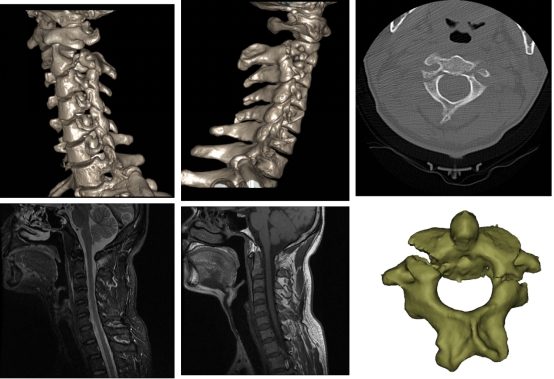

9.7日复查术后X片,患者李某可在床上自由翻身,患者周某恢复正常活动。

图4 术后情况

9.4日患者周某手术顺利完成;9.5日患者李某手术顺利完成。